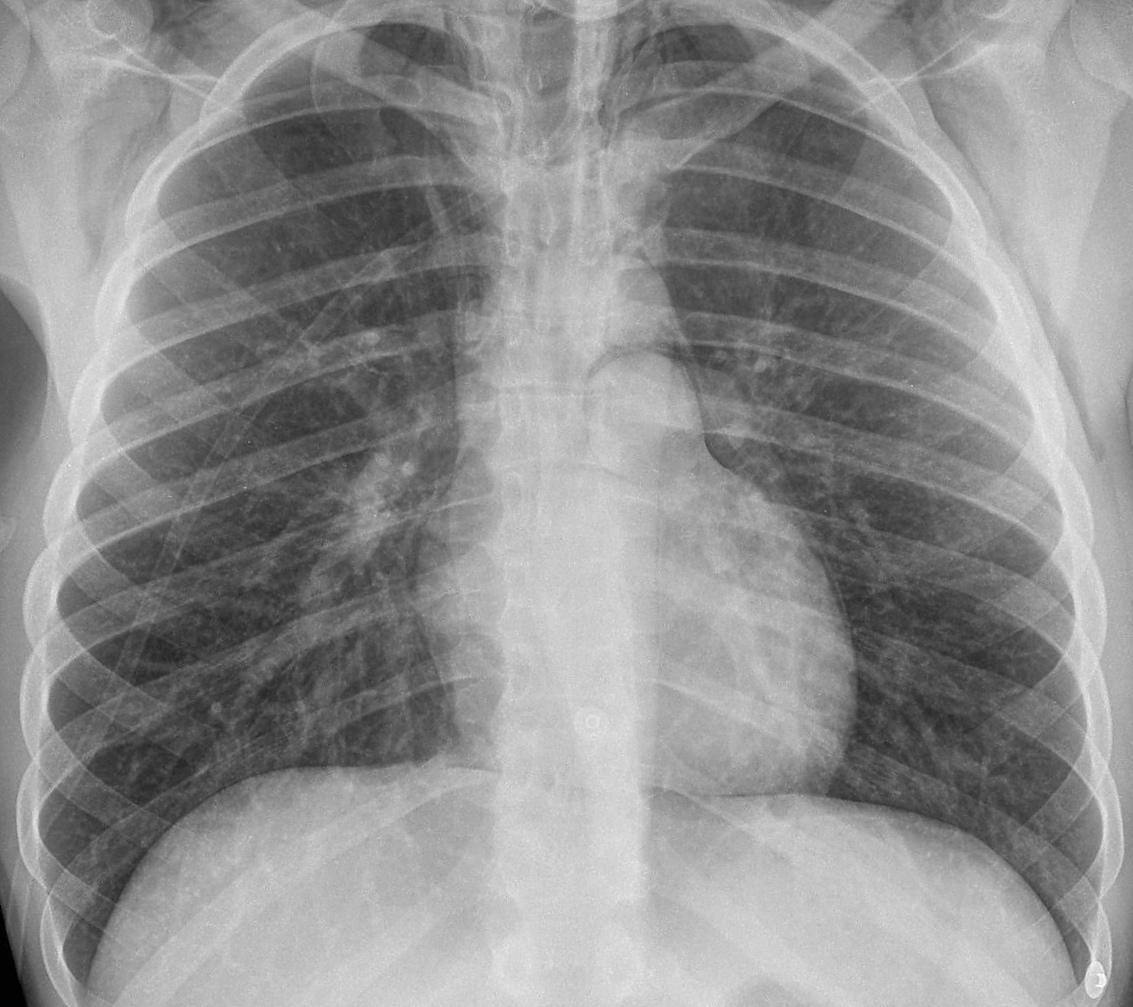

Lung Mets CXR